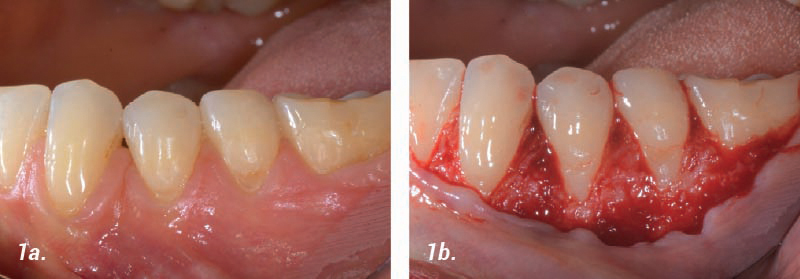

Cobertura de recesión múltiple

Caso aportado por el Dr. Thomas Pierchalla, Muenster, Alemania:

• 1a. Preoperatorio: Punto de partida.

• 1b. Cirugía: Colgajo abierto (protocolo CAF).